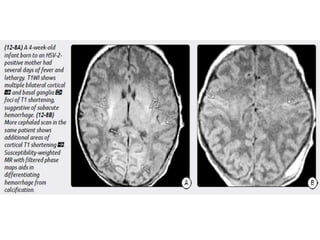

Herpes Simplex Virus

Imaging

Unlike childhood or adult HSE, neonatal HSV CNS infection is much

more diffuse. Both gray and white matter are affected.

Consider neonatal HSV encephalitis when cranial imaging at 2-3 weeks of

neonatal life

shows unexplained diffuse cerebral edema, with leptomeningeal

enhancement, without or with cerebral parenchymal hemorrhage.

Herpes Simplex Virus Imaging Unlikechildhood or adult HSE, neonatal HSV CNS infection is much more diffuse. Both gray and white matter are affected. Consider neonatal HSV encephalitis when cranial imaging at 2-3 weeks of neonatal life shows unexplained diffuse cerebral edema, with leptomeningeal enhancement, without or with cerebral parenchymal hemorrhage.